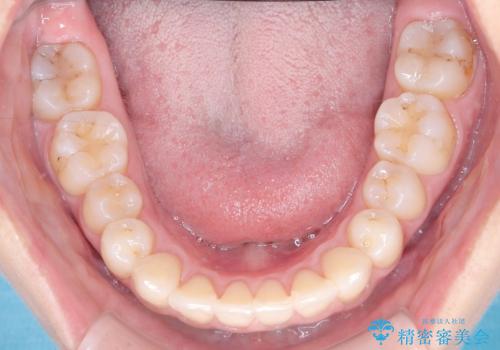

右下第二小臼歯の舌側転移の改善

- 患者様は、右下第二小臼歯が舌側に転移していることが主訴でした。診断の結果、抜歯を伴う矯正治療も検討しましたが、奥歯の遠心移動とIPR(インタープロキシマルリダクション)を行うことで、非抜歯で矯正を進めることが可能であると判断しました。治療計画では、審美ワイヤーを用いた2年間の治療で、歯列を整えつつ、臼歯関係や正中のバランスを維持しながら進めました。

非抜歯矯正では、歯の動きを慎重に調整することが求められます。本症例では、奥歯を遠心に移動させることで、舌側に転移した右下第二小臼歯の位置を改善しました。また、IPRを行うことで歯間スペースを確保し、無理なく歯列の調整を行いました。非抜歯での治療は、特に臼歯関係や正中を保ちながら治療できるというメリットがあり、最終的にはバランスの取れた歯並びを実現できました。審美ワイヤーを使用したことで、治療中も目立ちにくく、患者様の見た目にも配慮した治療を行いました。